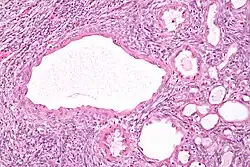

| Micrograph of a cystic nephroma (left of image). Normal kidney is seen on the right. H&E stain. | |

The characteristics of cystic nephromas are:

- Cysts lined by a simple epithelium with a hobnail morphology, i.e. the nuclei of the cyst lining epithelium bulges into the lumen of the cysts,

- Ovarian-like stroma that has a:

- Spindle cell morphology, and has a

- Basophilic cytoplasm.